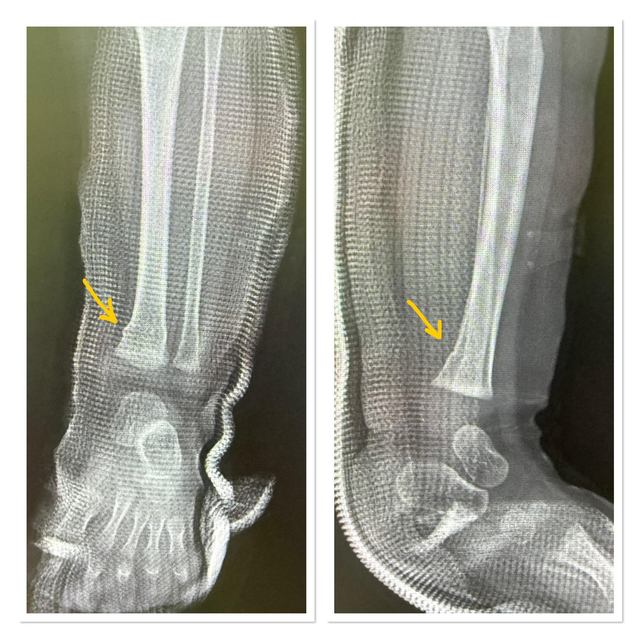

Hôm 21/4, một bác sĩ Thái Lan đã chia sẻ câu chuyện bi thảm mà ông được chứng kiến trên trang Facebook của Bệnh viện chỉnh hình Yingyos. Ông giải thích rằng ông đã đến thăm đứa trẻ khi bé được đưa vào bệnh viện sau vụ tai nạn. Sau khi xem xét phim chụp X-quang, ông thấy rằng tình trạng của cậu bé không nghiêm trọng. Đứa trẻ bị gãy xương nhẹ, chỉ mất khoảng ba đến bốn tuần để lành hoàn toàn mà không cần phẫu thuật.

Cậu bé may mắn chỉ bị gãy xương nhẹ, sẽ dần lành lại mà không cần phẫu thuật.